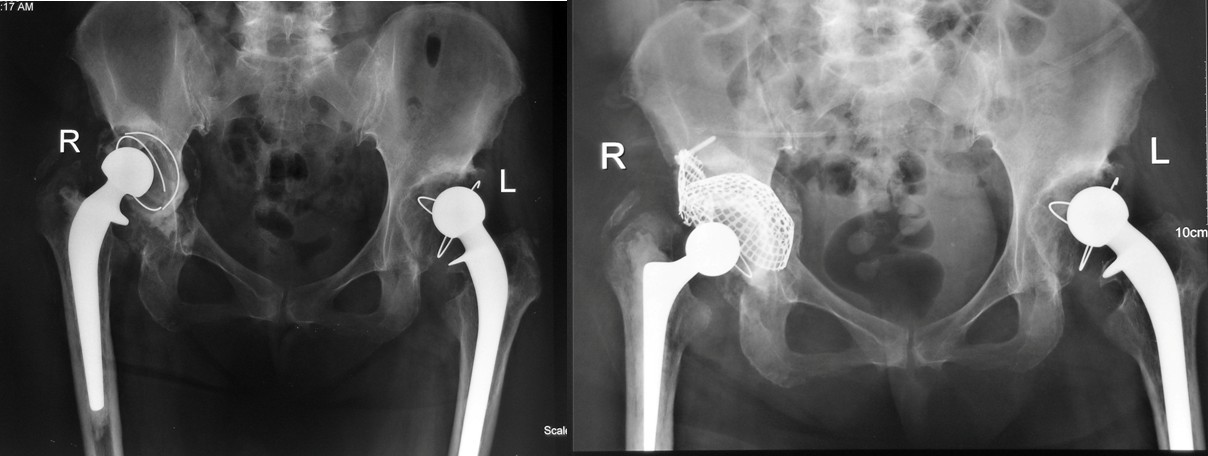

⑴Ⅰ型缺损:髋臼发育不良合并骨性关节炎,髋臼上缘Ⅰ型骨缺损,以金属网包含上缘缺损螺钉固定后,打压植骨,三代骨水泥技术全髋关节置换。

⑵Ⅱ型缺损:类风湿性关节炎合并髋臼内陷,髋臼缘完好。行颗粒骨打压植骨,三代骨水泥技术髋关节置换。

⑶Ⅲ型缺损:右髋关节置换术后骨溶解、假体无菌性松动造成髋臼巨大Ⅲ型骨缺损,行翻修术,以金属网包含髋臼上缘及髋臼内壁后,打压植骨,三代骨水泥技术全髋关节置换。